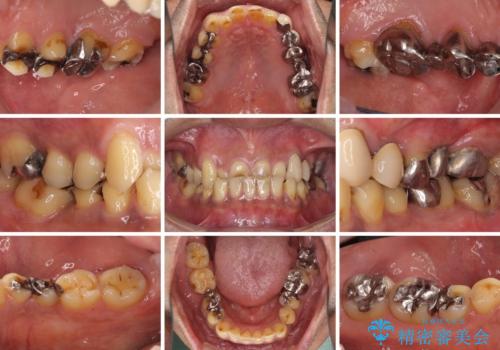

反対咬合ですり減った前歯とむし歯だらけの奥歯 総合歯科治療

- すり減った前歯や奥歯の銀歯を気にして来院された患者様です。

骨格的な反対咬合により上顎前歯の先端が顕著にすり減っている状態でした。

奥歯の欠損が散見されており、銀歯の装着されている歯も多いため、ワイヤー矯正にて歯列を調整し、その後オールセラミッククラウンにて補綴治療を行うこととしました。

反対咬合改善には奥歯の咬み合わせをしっかりと改善させることが必要となりますが、奥歯に欠損が多いため、矯正治療が難航することが予想されます。